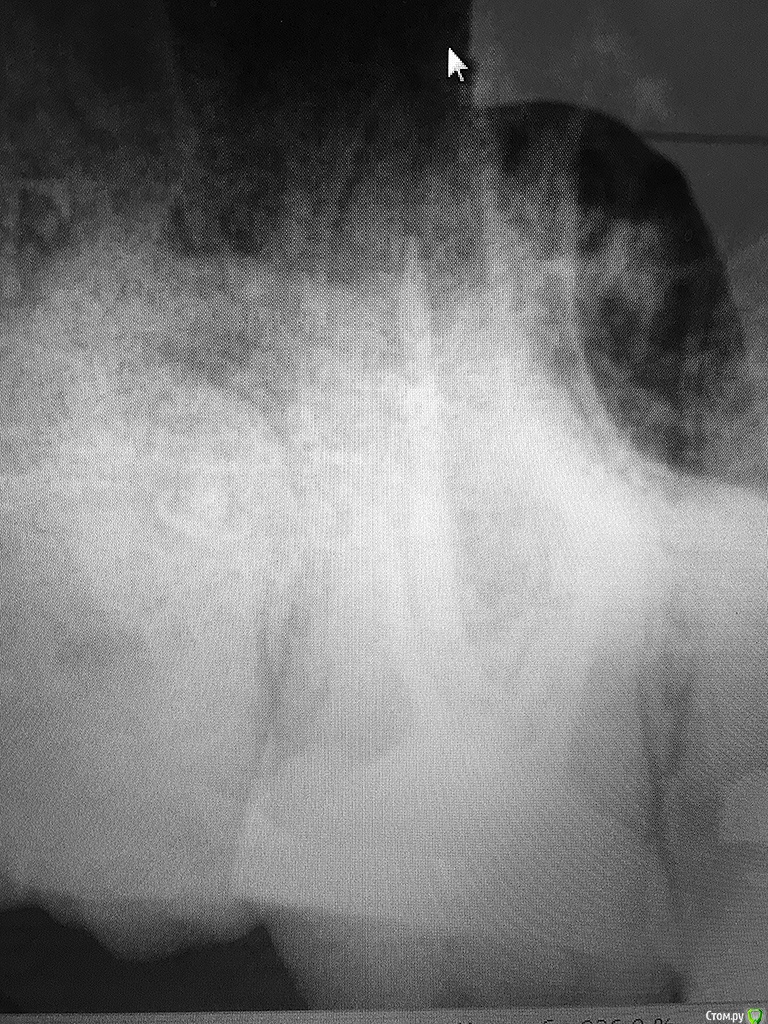

rozmari Опубликовано 20 марта, 2017 Поделиться Опубликовано 20 марта, 2017 Здравствуйте люди добрые.), пытаюсь пролечить верхнюю 7-ку с 14 октября (5 месяцев).Коротко о наболевшем:1. 10 октября выпала пломба, 14 октября пролечил кариес.После лечения зуб ныл после еды, ждали с врачом 1.5 месяца, но боли не прошли.2. 2 декабря положили лекарство, 16 декабря депульпировали зуб, прочистили 3 канала. Далее болей и нытья после еды нет, но не проходит чувствительность зуба, даже на легкое постукивание ногтем с любой стороны, так же неприятно реагирует на зубную щетку....ждемс3. 27 февраля симптомы не проходят, врач говорит пропить 3 дня Найс, пропито, ничего не изменилось. меняю клинику... 4. 9 марта делаю снимок №1 обнаруживаем не долеченный нёбный канал, чистим, ставим временную пломбу 5. 19 марта симптомы не изменились, 2 часа пытаемся прочистить оставшиеся 2 канала (безуспешно), зато с большими сомнениями, но вроде как нашли 4й канал(снимок №3), чистим и ставим временную пломбу. продолжение следует.....на приём через неделю п.с. вижу что качество снимков оставляет желать лучшее, но всё же буду очень благодарен любому совету. Ссылка на комментарий

St. Опубликовано 20 марта, 2017 Поделиться Опубликовано 20 марта, 2017 п.с. вижу что качество снимков оставляет желать лучшее, но всё же буду очень благодарен любому совету. По предоставленным снимкам совсем ничего не видно.. Ссылка на комментарий